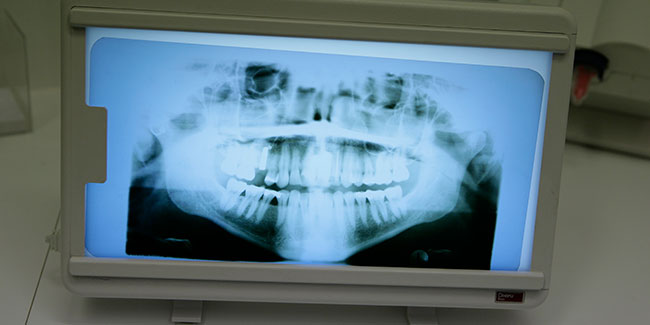

Chirurgische Maßnahmen umfassen Eingriffe an Zähnen, Zahnfleisch und Kieferknochen – einschließlich dem Einsetzen von Implantaten. Dabei achten wir nicht nur auf eine erfolgreiche Behandlung, sondern ebenso auf ein möglichst schonendes Vorgehen und eine angenehme Betreuung.

Moderne Technik, viel Erfahrung und durchdachte Abläufe sorgen dafür, dass selbst komplexere Eingriffe sicher und präzise durchgeführt werden können.